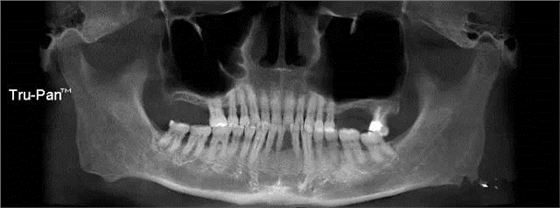

第二圖:上頜竇氣化,導(dǎo)致上頜竇很大,骨高度不足,但是上頜竇底平,粘膜很干凈。適合外提升或者高手可行內(nèi)提升。(還有二次內(nèi)提升)。